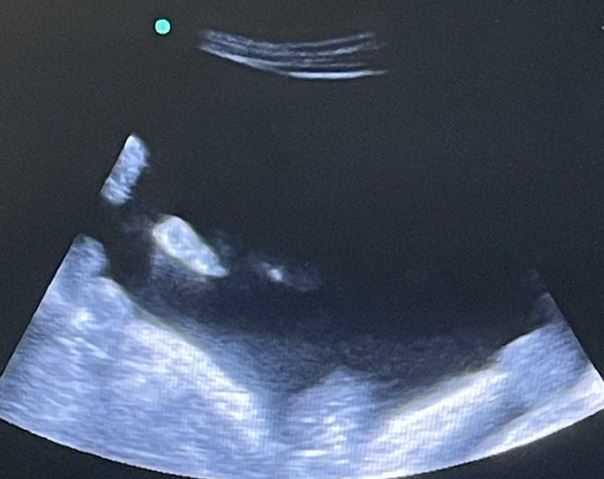

Pruebas complementarias: Analítica: Hb 13 g/dL sin leucocitosis, fibrinógeno 599 mg/dL, TP 20,3s, TTP 31s, gasometría arterial normal, Bb 1,5 mg/dL a expensas de directa 0,7 mg/dL, AST 57 UI/L, GGT 13 UI/l, LDH 152 UI/L, PCR 5 mg/dL. Rx de Tórax y Rx de Abdomen normales. ECG: RS con HBAI con extrasístoles auriculares. Ecografía a pie de cama: abundante líquido libre en cavidad peritoneal y correderas parietocólicas.

Se realiza ecografía para proceder con la paracentesis evacuadora de forma segura, obteniéndose 4200 cc de líquido ascítico claro y se pautan 3 ampollas de albúmina 20%.